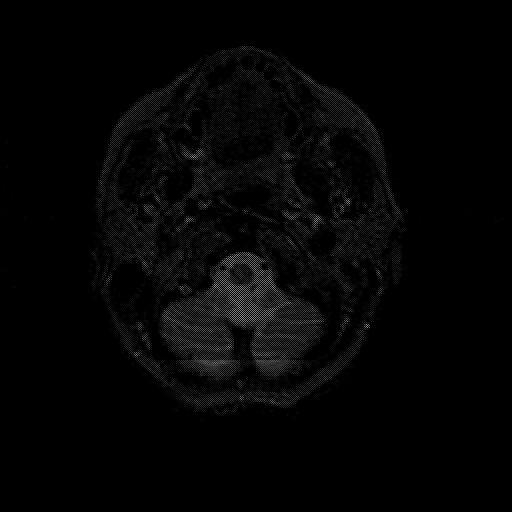

overlay 1: Slice 5

Slice 5

MRCBFCBF with

T1PDT2T1PDT2